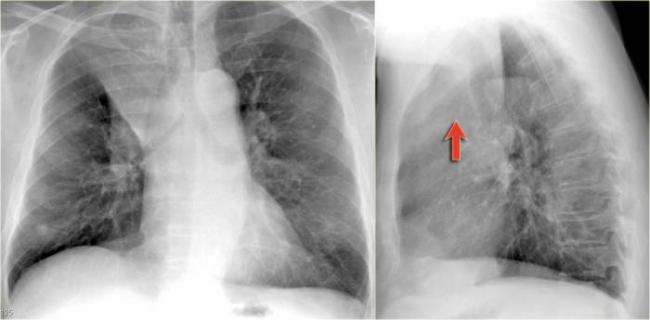

На рентгеновских снимках выявляют следующие признаки, указывающие на спадение легочной ткани:

Однородное затемнение в области поражения. Размеры тени зависят от вида ателектаза: при долевом выявляется обширное затемнение, при сегментарном — в виде клина или треугольника, расположенного вершиной к корню легкого, дольковые ателектазы множественные и похожи на очаговую пневмонию. Дистензионный ателектаз расположен низко, около диафрагмы, имеет небольшие размеры и вид поперечных полос или темных дисков. Смещение органов: при компрессионном ателектазе смещение наблюдается в здоровую сторону, так как на стороне поражения давление больше, при обтурационном, наоборот – смещение будет в сторону ателектаза, так как на стороне поражения нарастает притягивающее отрицательное давление. Подъем купола диафрагмы – это видно по расположению печени.

Помимо всего перечисленного выше, рентгеноскопия, то есть исследование «вживую», позволяет увидеть куда смещаются органы в зависимости от фазы дыхания, кашля. Это является дополнительным признаком ателектаза, помогающим выявить тип болезни.

Предварительным, рентгенологическим диагнозом является «синдром правой доли», при котором выявляется затемнение площади средней доли правого легкого.

Частое возникновение ателектаза правого легкого связано с анатомическими особенностями правого среднедолевого бронха: он узкий и длинный, поэтому часто происходит его перекрытие при патологическом процессе.